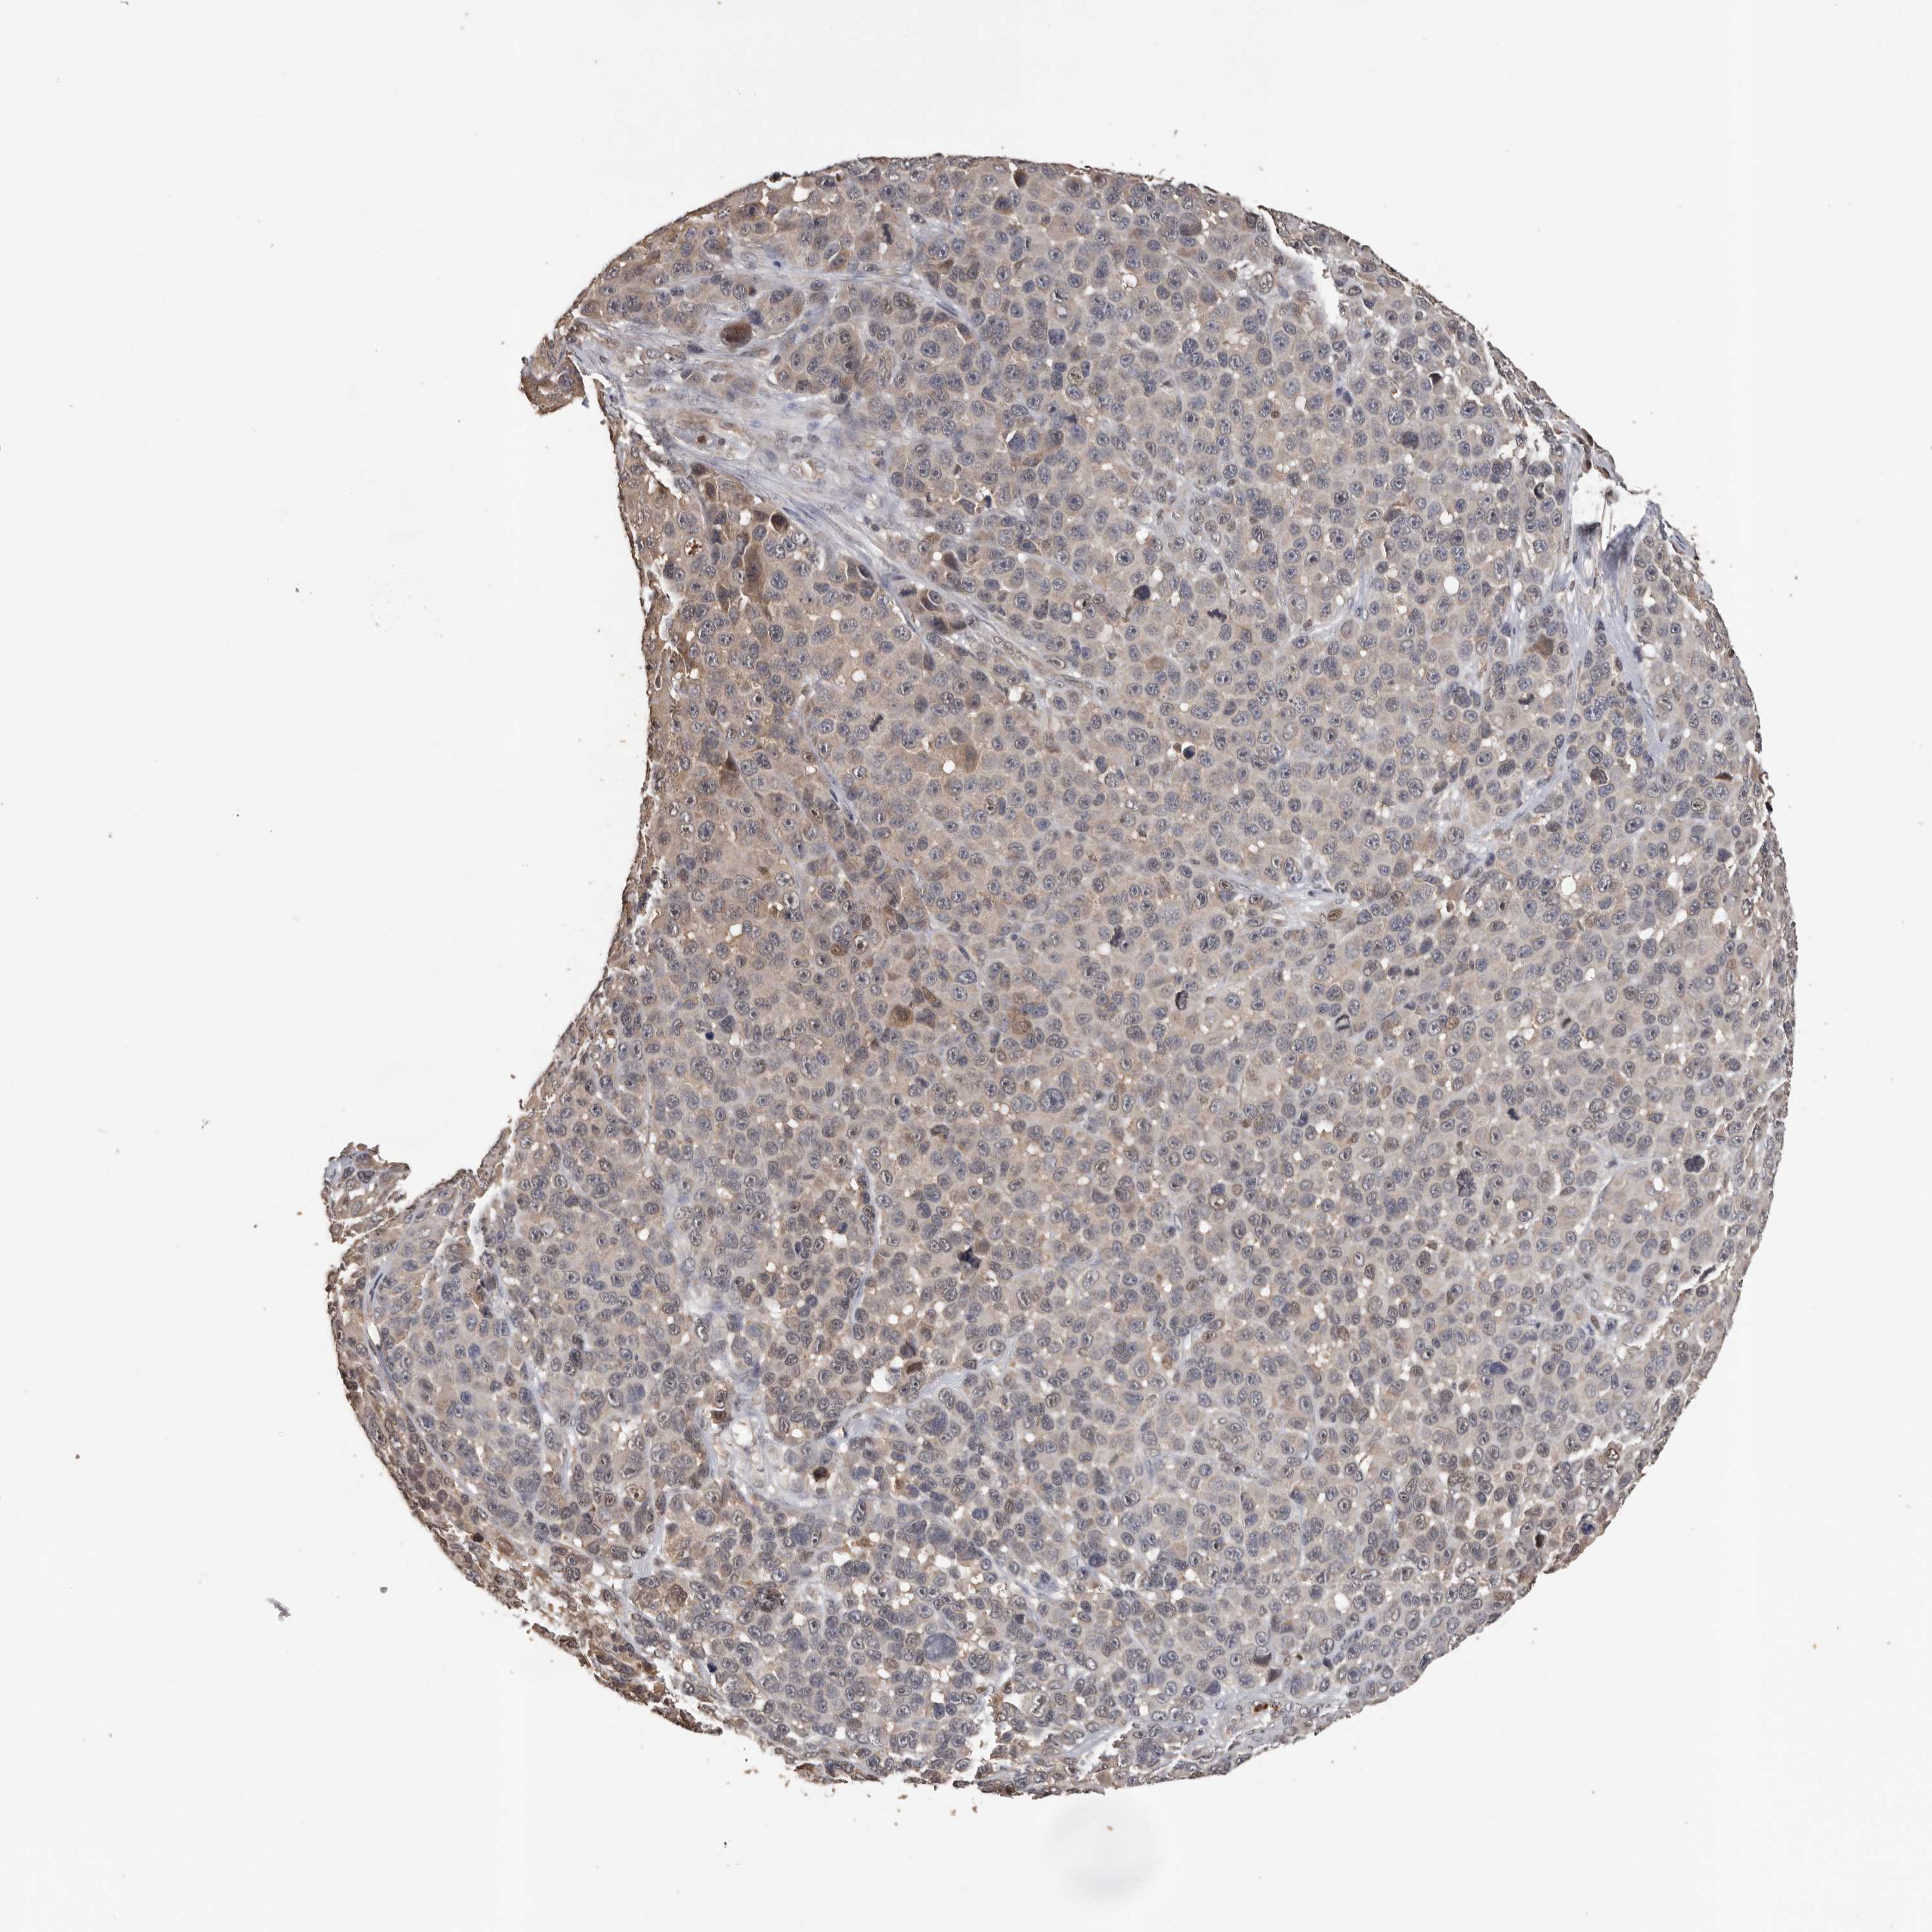

MELANOMA - Protein expressioni

A mouse-over function shows sample information and annotation data. Click on an image to view it in a full screen mode. Samples can be filtered based on level of antibody staining by selecting one or several of the following categories: high, medium, low and not detected. The assay and annotation is described here.

Note that samples used for immunohistochemistry by the Human Protein Atlas do not correspond to samples in the TCGA dataset.

Antibody stainingi

Antibody staining in the annotated cell types in the current human tissue is reported as not detected, low, medium, or high, based on conventional immunohistochemistry profiling in selected tissues. This score is based on the combination of the staining intensity and fraction of stained cells.

Each image is clickable and will lead to virtual microscopy that enables deeper exploration of all samples and also displays staining intensity scores, fraction scores and subcellular localization as well as patient and tissue information for each sample.

Antibody HPA023081

Antibody HPA023103

Antibody HPA024795

Staining

High

Medium

Low

Not detected

Intensity

Strong

Moderate

Weak

Negative

Quantity

>75%

75%-25%

<25%

None

Location

Nuclear

Cytoplasmic/membranous

Cytoplasmic/membranous,nuclear

Malignant melanoma, NOS

Malignant melanoma, Metastatic site